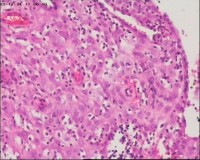

性别

女

年龄

20岁

停经3月,阴道不规则流血7天。

宫刮物

灰白灰红碎组织一堆,大小为7*6*1cm,部分组织呈水泡状

水肿的绒毛和蜕膜,没看到增生的滋养细胞。必要时可做IHC除外部分葡萄胎,并结合临床HCG。

考虑葡萄胎